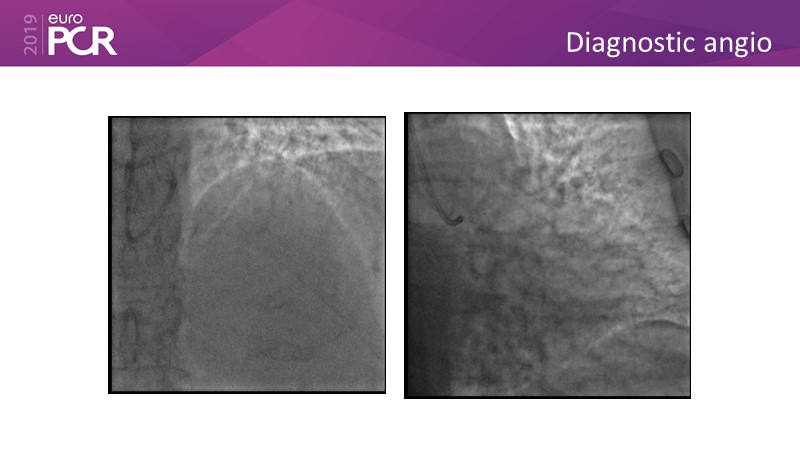

Distal left main stenosis: how to treat optimally with dedicated bifurcation stent BiOSS Lim C. Case-based session

Consult this session to learn more about the multiple technological options with dedicated bifurcation stent for complex left main bifurcation lesions, and the applicability of this stent for the different clinical presentations.

- To get acquainted with the new technology for bifurcation lesion

- To learn about multiple technological options with dedicated bifurcation stent for complex left main bifurcation lesions

- To learn about applicability of the dedicated bifurcation stent for the different clinical presentations